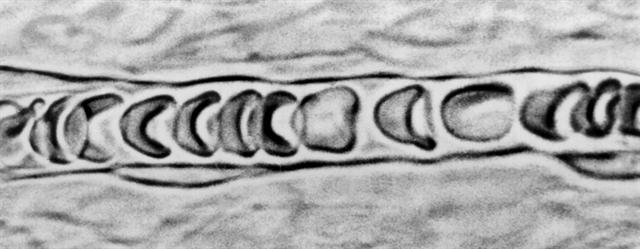

Рис. 1. Прижизненная микроскопия: поток эритроцитов в кровеносном капилляре.